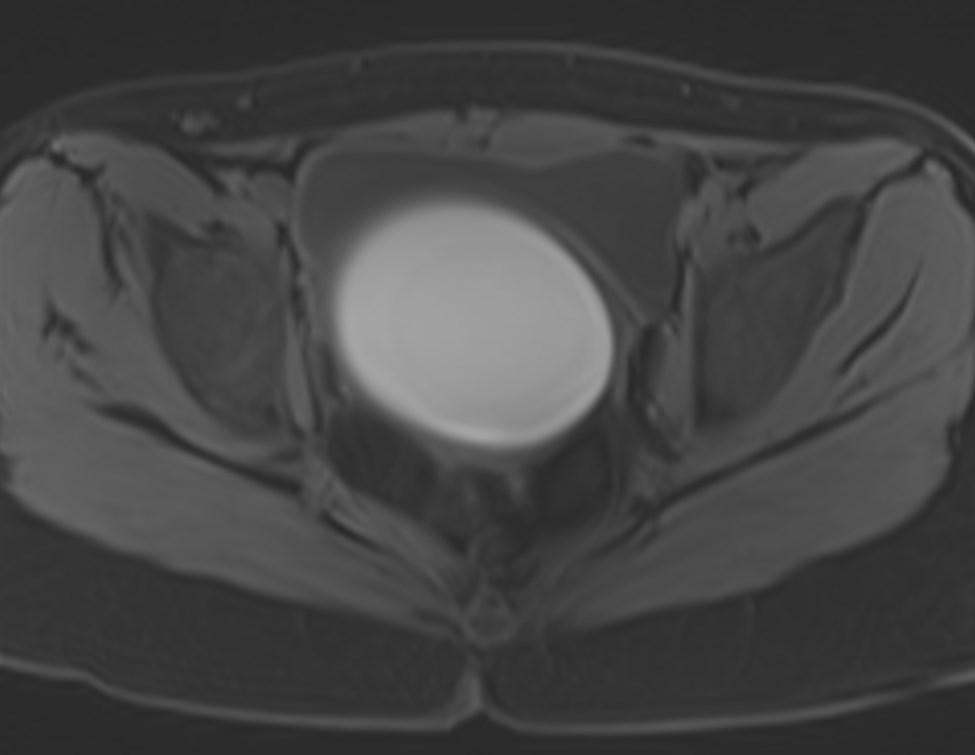

MR images showed hemorrhagic fluid in a distended vagina. The uterine cavity is not dilated.

In haematocolpos, there is accumulation of menstrual blood in the vagina in the setting of an anatomical obstruction, usually an imperforate hymen. When there is concurrent uterine distention, the term haematometrocolpos is used.